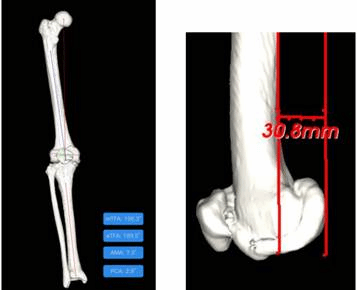

(图一)通过AIJOINT进行术前精准定位

(图二)模拟截骨后假体安放